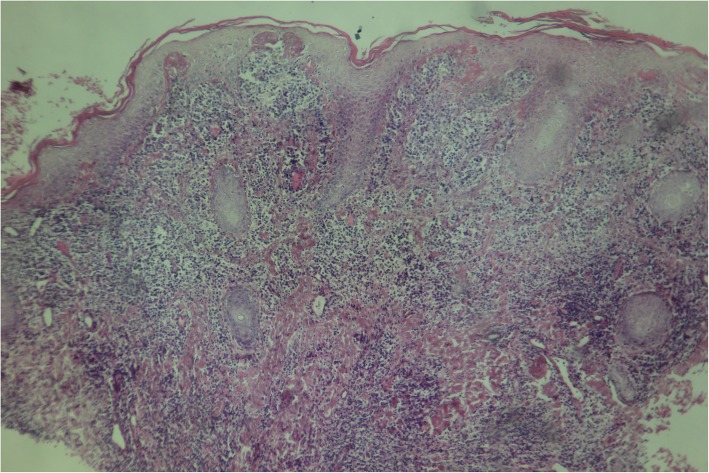

요스의 생검에 대한 현미경 검사는 명확한 표피 과형성(피부 비후의 일종)과 유두종증(표면 불규칙의 일종)을 보일 수 있으며, 종종 국소적인 해면화(표피의 특정 부분에 체액이 축적되는 것)를 동반한다. 면역 체계 세포, 호중구 및 형질 세포가 피부에 축적되어 미세 농양을 유발할 수 있다.

Warthin–Starry 염색 또는 Levaditi 은 염색은 ''T. pallidum''을 선택적으로 염색하며, 직접 및 간접 면역형광 검사 및 면역과산화효소 검사는 ''T. pallidum''에 대한 다클론 항체를 검출할 수 있다. 조직학은 종종 요스와 매독을 구별하는 몇 가지 공간적 특징을 보여준다(매독은 표피가 아닌 진피에서 발견될 가능성이 더 높으며 더 많은 내피 세포 증식과 혈관 폐쇄를 보입니다).[2]

진단은 대개 임상적으로 이루어진다.[20] 특징적인 피부 병변의 모양과 분포, 환자의 병력(유행 지역 거주 또는 여행) 등을 종합하여 진단한다. 초기 병변, 특히 궤양성 병변[20]에서 채취한 표본을 암시야 현미경 검사하면 원인균을 확인할 수 있다. 스피로헤타는 폭이 0.3μm, 길이가 6–20μm에 불과하여 일반 광학 현미경으로는 관찰이 어렵다.[2]요스 생검에 대한 현미경 검사는 뚜렷한 표피 과형성(피부 비후의 일종)과 유두종증(표면 불규칙의 일종)을 보이며, 국소적인 해면화(표피의 특정 부분에 체액이 축적되는 것)를 동반하기도 한다. 면역 체계 세포, 호중구 및 형질 세포가 피부에 축적되어 미세 농양을 유발할 수 있다.

Warthin–Starry 염색 또는 Levaditi 은 염색은 ''T. pallidum''을 선택적으로 염색하며, 직접 및 간접 면역형광 검사 및 면역과산화효소 검사는 ''T. pallidum''에 대한 다클론 항체를 검출할 수 있다. 조직학은 요스와 매독을 구별하는 몇 가지 공간적 특징을 보여주는데, 매독은 표피가 아닌 진피에서 발견될 가능성이 더 높으며 더 많은 내피 세포 증식과 혈관 폐쇄를 보인다.[2]

요스의 생검에 대한 현미경 검사는 명확한 표피 과형성(피부 비후의 일종)과 유두종증(표면 불규칙의 일종)을 보일 수 있으며, 종종 국소적인 해면화(표피의 특정 부분에 체액이 축적되는 것)를 동반한다.[2] 면역 체계 세포, 호중구 및 형질 세포가 피부에 축적되어 미세 농양을 유발할 수 있다.Warthin–Starry 염색 또는 Levaditi 은 염색은 트레포네마 팔리덤(''T. pallidum'')을 선택적으로 염색하며, 직접 및 간접 면역형광 검사 및 면역과산화효소 검사는 ''T. pallidum''에 대한 다클론 항체를 검출할 수 있다.[2]